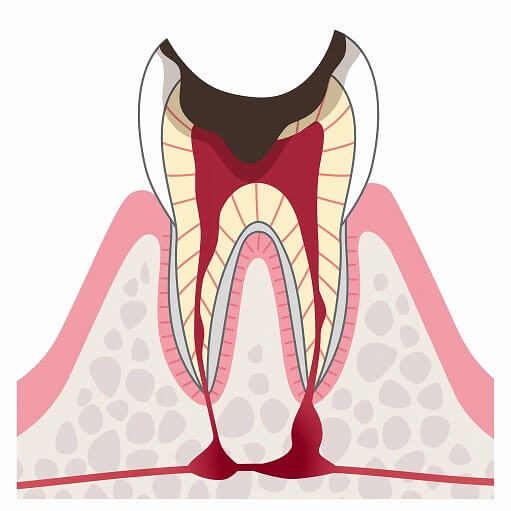

C3

C3は象牙質を突き抜け、歯の神経(歯髄)にまでむし歯が進行してしまった状態です。冷たいものや熱いものが染みるだけでなく、夜眠れないほどの強い痛みが出る場合もあります。C3の状態まで達してしまうと歯の神経への治療が必要となるため、治療回数は多くなります。

C3は象牙質を突き抜け、歯の神経(歯髄)にまでむし歯が進行してしまった状態です。冷たいものや熱いものが染みるだけでなく、夜眠れないほどの強い痛みが出る場合もあります。C3の状態まで達してしまうと歯の神経への治療が必要となるため、治療回数は多くなります。

C4

C4はむし歯が進行してしまったことにより歯の頭が崩れ落ちてしまい、歯の根だけが残っている状態です。歯の神経が死んでしまっているため痛みが無い場合もありますが、歯の根の奥にまでむし歯菌が到達すると激痛が起こることもあり、場合によってや顔の腫れや高熱が出ることもあります。進行度合いによっては歯を抜かないといけないことがあります。

C4はむし歯が進行してしまったことにより歯の頭が崩れ落ちてしまい、歯の根だけが残っている状態です。歯の神経が死んでしまっているため痛みが無い場合もありますが、歯の根の奥にまでむし歯菌が到達すると激痛が起こることもあり、場合によってや顔の腫れや高熱が出ることもあります。進行度合いによっては歯を抜かないといけないことがあります。